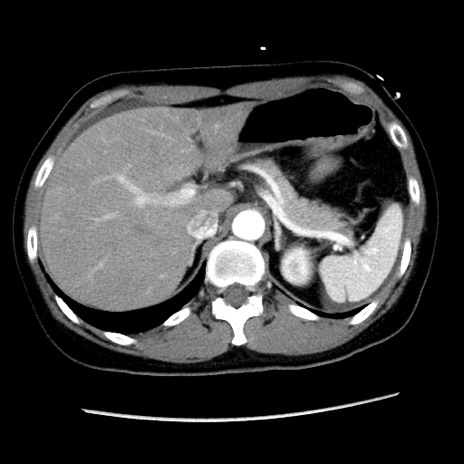

冠状断像

矢状断像